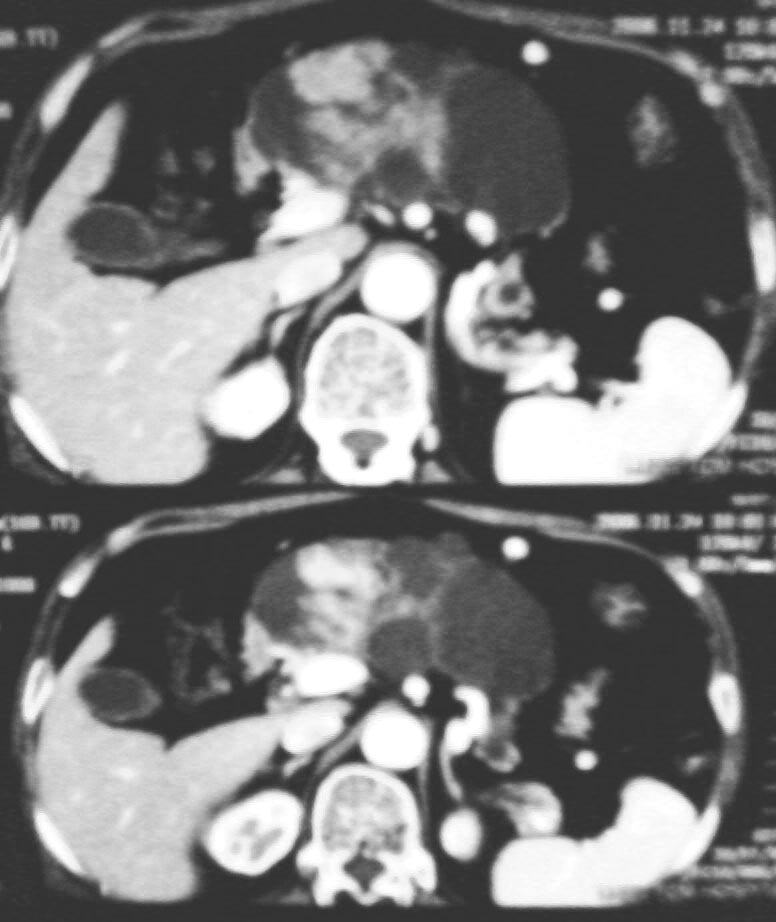

上腹部不适半年左右,体检此区压痛,精神状态很好,谢各位给个意见!

与中国医学影像网中“今日病例”(12-2)类似——胰管乳头状粘液瘤。

考虑胰腺黏液腺癌.低度恶性.

考虑胰管乳头状粘液瘤

胰腺占位病灶

1与中国医学影像网中“今日病例”(12-2)类似——胰管乳头状粘液瘤

2考虑胰腺黏液腺癌.低度恶性.